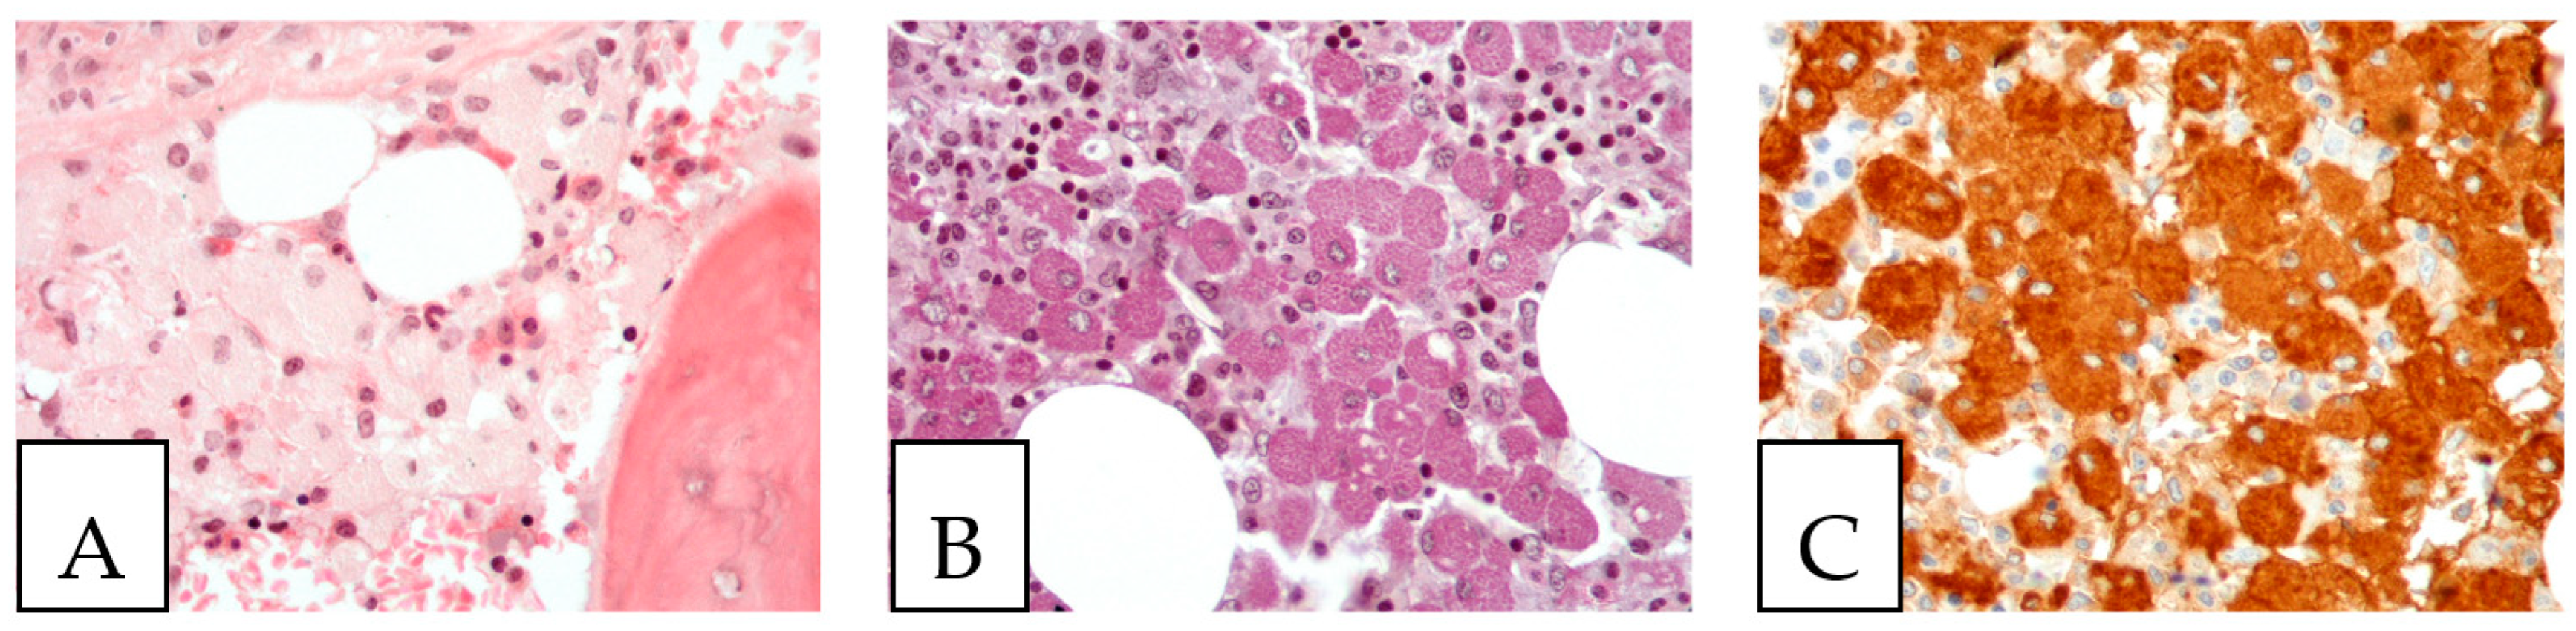

5. Pathologic Features